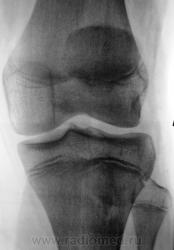

Пациент был направлен на рентгеновское исследования обоих коленных суставов по поводу болеши "Осгут-Шлаттера"

Нет, я был не прав, что утверждал, что на прямой рентгенограмме бугристость не отображается. Мы, на пленке уже вообще не работаем, оказалось, что на "цифре" на прямой отображается и ох, как хорошо.

Да и на пленке отображается )))

Кроме остеохондропатии бугристостей у пациента явная латеропозизия надколенников и бугристостей большеберцовых костей, что свидетельствует о дисплазии мыщелков бедренных костей, вероятнее всего клинически проявляющаяся болями в переднем отделе коленных суставов (под надколенниками).